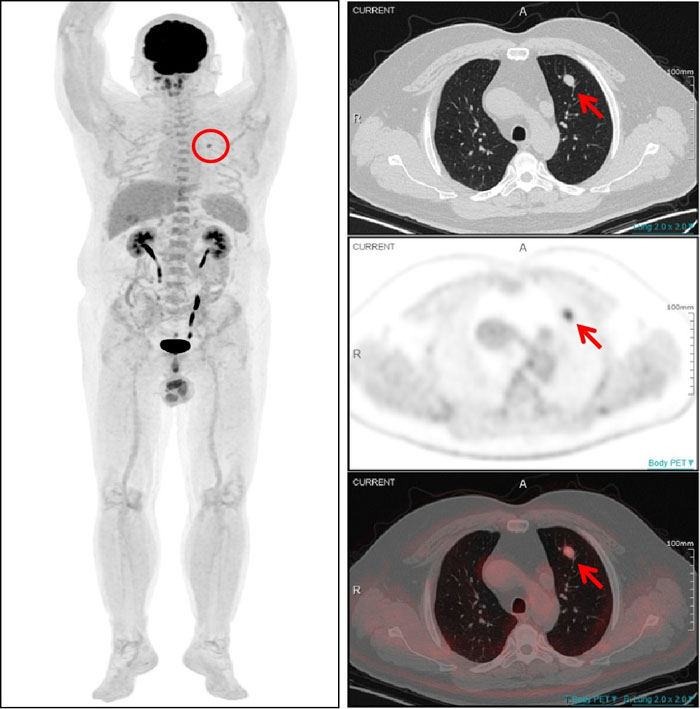

PET/CT顯示:該結節伴明顯異常葡萄糖高代謝(SUVmax4.5),為肺轉移灶。

?一名54歲男性患者曾在1年半前接受了左大腿脂肪肉瘤切除術,術后規律復查。一次常規CT檢查發現其左肺上葉存在一個軟組織結節,隨后復查顯示該結節有所增大,直徑約為1.0cm。面對這一疑似轉移的挑戰,全景動態Total-body PET/CT 清晰顯示左肺上葉結節伴明顯異常葡萄糖高代謝,提示該結節為肺轉移灶。基于檢查結果,醫生能夠及時為患者制定更加個體化的治療方案。對該患者的診斷,彰顯了全景動態Total-body PET/CT 在癌癥診斷領域的非凡實力。